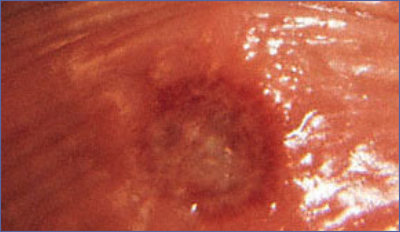

Genital Herpes Simpleks Enfeksiyonu

(genital "uçuk" hastalığı)

Hem ABD’de hem de dünya çapında genital herpes çok yaygındır. 1970'ler ile 1990'ların başı arasında, genital herpes enfeksiyonu olan Amerikalı oranı % 30 lara ulaştı, maalesef en büyük artış ergenlik çağlarındaki kişiler arasındaydı. En son çalışmalarda en azından 12 yaşında ve daha büyük 45 milyon kişide bu enfeksiyonun olduğunu gösteriyor. Bu, her 3 kişiden birinin enfekte olduğunu gösteriyor. Genital herpes, dudak çevresinde görülen uçuk hastalığına benzer lezyonların çok sayıda ve grup halinde ve daha şiddetli belirtilerle genital bölgede ortaya çıkmasıdır. Dudak uçuğuna yol açan Tip 1 Herpes Simpleks virüsü HSV 1 tarafından oluşturulabileceği gibi daha sık olarak cinsel temasla geçen HSV 2 tarafından oluşturulur. Uçuklar kişi enfekte olduktan 4-7 gün sonra ortaya çıkar. Genital herpes çok bulaşıcı cinsel bir hastalıkdır ve herhangi bir seks biçimi veya cinsel ilişki ile yayılır. Genital herpesin tedavisi yoktur. Oral herpesi olan biri ile cinsel ilişkiye giren kişinin de genital herpes riski vardır. Dokunma cinsel ilişki ve öpüşme virusun yayılmasına neden olabilir Virüs bir kez vücuda yerleştiğinde belli dönemlerde tekrarlayıcı enfeksiyonlara yol açar. Enfeksiyon ilk başladığında lezyonların hem ağrısı hem de süresi daha uzundur, zamanla ağrıların şiddeti ve sıklığı azalır. Bu enfeksiyonun en önemli tarafı gebelik döneminin sonlarında ortaya çıktığında, doğum kanalından bebeğe bulaşarak bebekte ciddi sinirsel hasarlar ve ölüme neden olabilmesidir. Aktif enfeksiyon varsa bu nedenle sezaryen ile doğum gerekir.